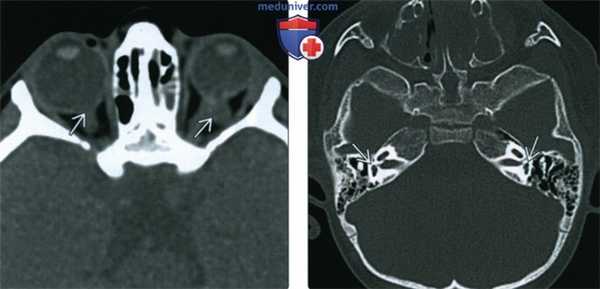

(Слева) При аксиальной КТ без контрастного усиления у этого же ребенка с синдромом CHARGE визуализируются двухсторонние колобомы, определяется левосторонняя микрофтальмия.

(Справа) При аксиальной КТ в костном окне у этого же ребенка с синдромом CHARGE определяются типичные двухсторонние аномалии лабиринта с уменьшением преддверий и отсутавием полукружных каналов.